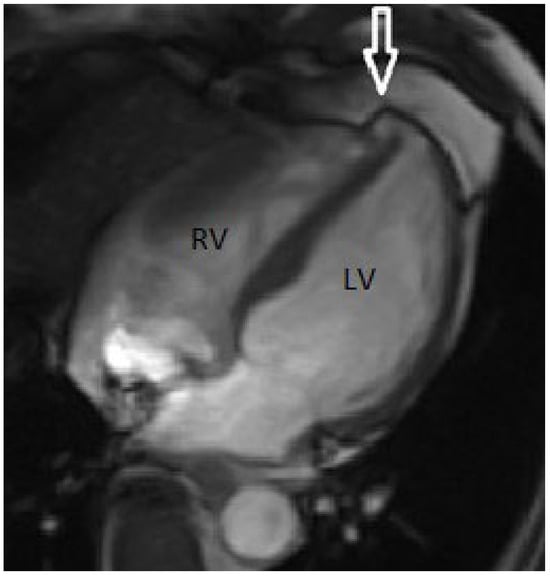

To clarify the nature of this finding, cardiac magnetic resonance imaging (MRI) was performed (Figure 4), which showed a small aneurismal cavity with a narrow neck and an extension of 6 mm at the septo-apical level, with extension under the right ventricular apex, no evidence of communication between the cavities and absence of scar.

Figure 4. Magnetic resonance imaging: evidence of a small diverticular pouch (white arrow) at the apex of the left ventricle with narrow walls, not associated with late enhancement and without presence of interventricular communication. LV = left ventricle; RV = right ventricle.